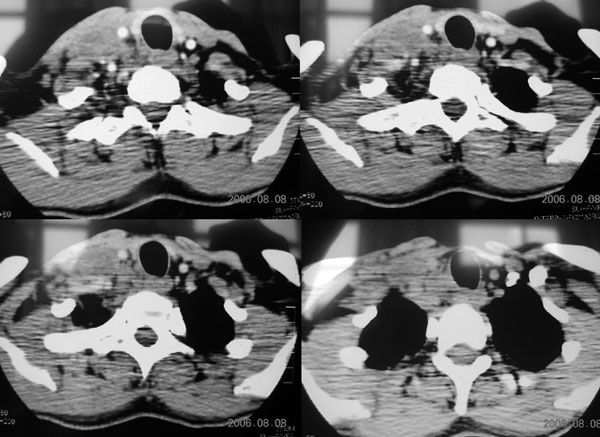

患者,谭××,男,35岁,右颈部肿痛一周,体温39度。增强待续,伪影大,对不起,请大家凑合……

生长于颈部2血管之间多房样壁强化明显。

生长于颈鞘部2血管之间的病灶,环状强化明显,见分隔。

生长于颈部2血管之间多房样壁强化明显,结合临床右颈部肿痛一周,体温39度,

考虑:炎性淋巴结肿大及炎性包块可能性大.